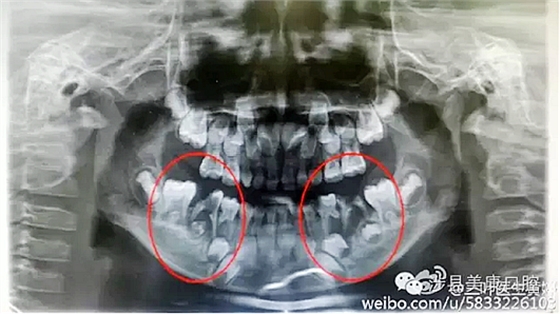

普通家長看了這張牙片估計(jì)能看出來孩子的牙不好,但是究竟不好到什么程度呢,讓葉子姐告訴大家:

上圖孩子的乳牙感染已經(jīng)將下面骨感染到吸收消失,并且直接影響到了下面的恒牙胚,家長們上點(diǎn)心吧。那些說乳牙不用治療,換牙就會(huì)好的人(包括醫(yī)生)還是睜開眼睛看看吧,不要自欺欺人,更不要用自己的錯(cuò)誤誤導(dǎo)他人誤導(dǎo)大眾。

網(wǎng)友又不明白了,什么叫吸收消失?看x片看不懂哎......

黑色部分表示那里的骨頭感染已經(jīng)爛沒有了,消失了,牙胚應(yīng)該在健康頜骨里孕育生長發(fā)育,現(xiàn)在在感染的病灶里生長,在膿水里侵泡。

又有好奇網(wǎng)友問他怎么有那么多牙?

乳牙下面有恒牙孕育著。